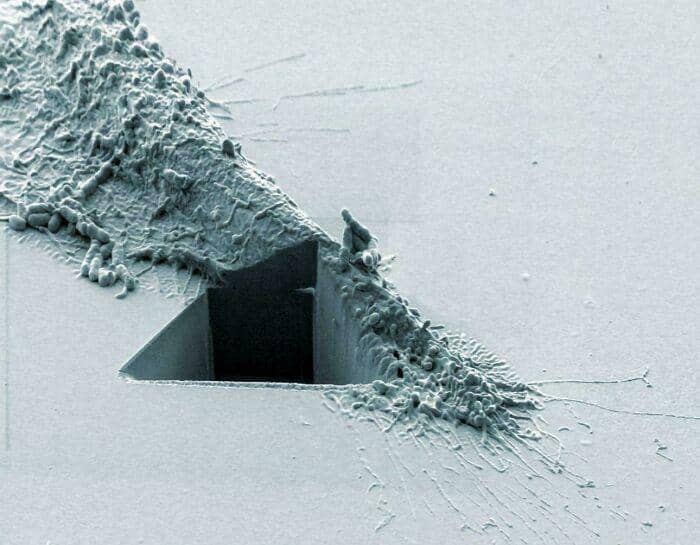

#36 Cancer Cell Hit By An Ion Beam